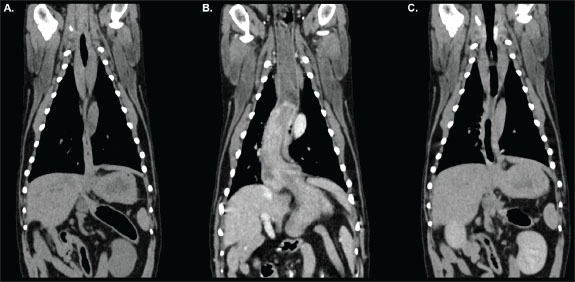

Pre-contrast acquisitions demonstrated a normally positioned stomach; however, the gastric fundus was cranially herniated through the oesophageal hiatus into the caudal esophageal lumen on the venous-phase post-contrast scan (Figs. 1 and 2). The distal oesophageal wall encircled part of the gastric fundus, creating a target-like appearance on transverse-plane images (Fig. 3). The orad oesophagus contained a small-to-moderate amount of heterogeneous fluid-to-soft-tissue-attenuating material. Delayed post-contrast images showed the stomach had returned to its normal anatomical position.

Fig. 2. Dorsal reconstructions of the thorax and cranial abdomen acquired during pre-contrast (A), venous-phase (B), and delayed post-contrast (C) phases of the study. The stomach is appropriately positioned with minimal distension of the oesophagus in the pre-contrast (A) and delayed (C) acquisitions. Gastroesophageal intussusception is identified during the venous-phase acquisition (B) as outlined in Figure 1.